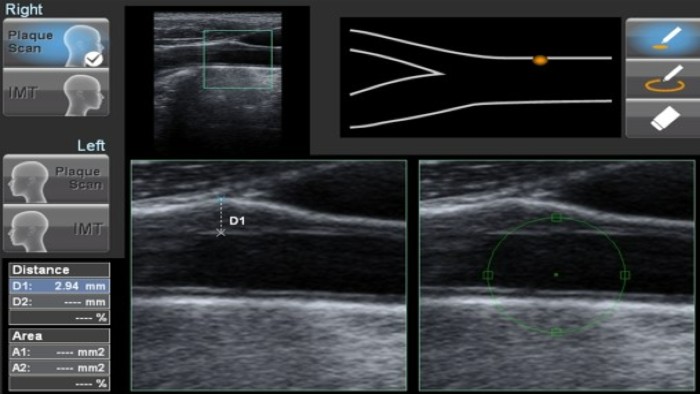

Specialist software and ultrasound imaging from the Cardiovascular research